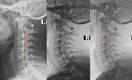

[Purpose] To present the successful structural improvement in cervical lordosis in a patient suffering from cervicogenic headache having cervical kyphosis. [Participant and Methods] A 26 year old female presented with the primary complaint of headache. Radiography demonstrated a cervical kyphosis. Chiropractic BioPhysics® methods were used to restore the cervical spine alignment. Twenty-five treatments were given over 8 weeks. A 2.5 year follow-up was also reported. [Results] Radiography showed a dramatic increase in cervical lordosis following initial treatment. The patient also reported substantial reductions in headache frequency and severity as well as other bodily improvements, reduced disability and improved quality of life. The long-term follow-up showed a maintenance of lordosis correction and patient wellness. [Conclusion] A cervical kyphosis was reversed back to a normal lordosis in 8 weeks and coincided with dramatic resolution of cervicogenic headache in a young female. The cervical lordosis may be a key biomechanical biomarker in cervicogenic headache.